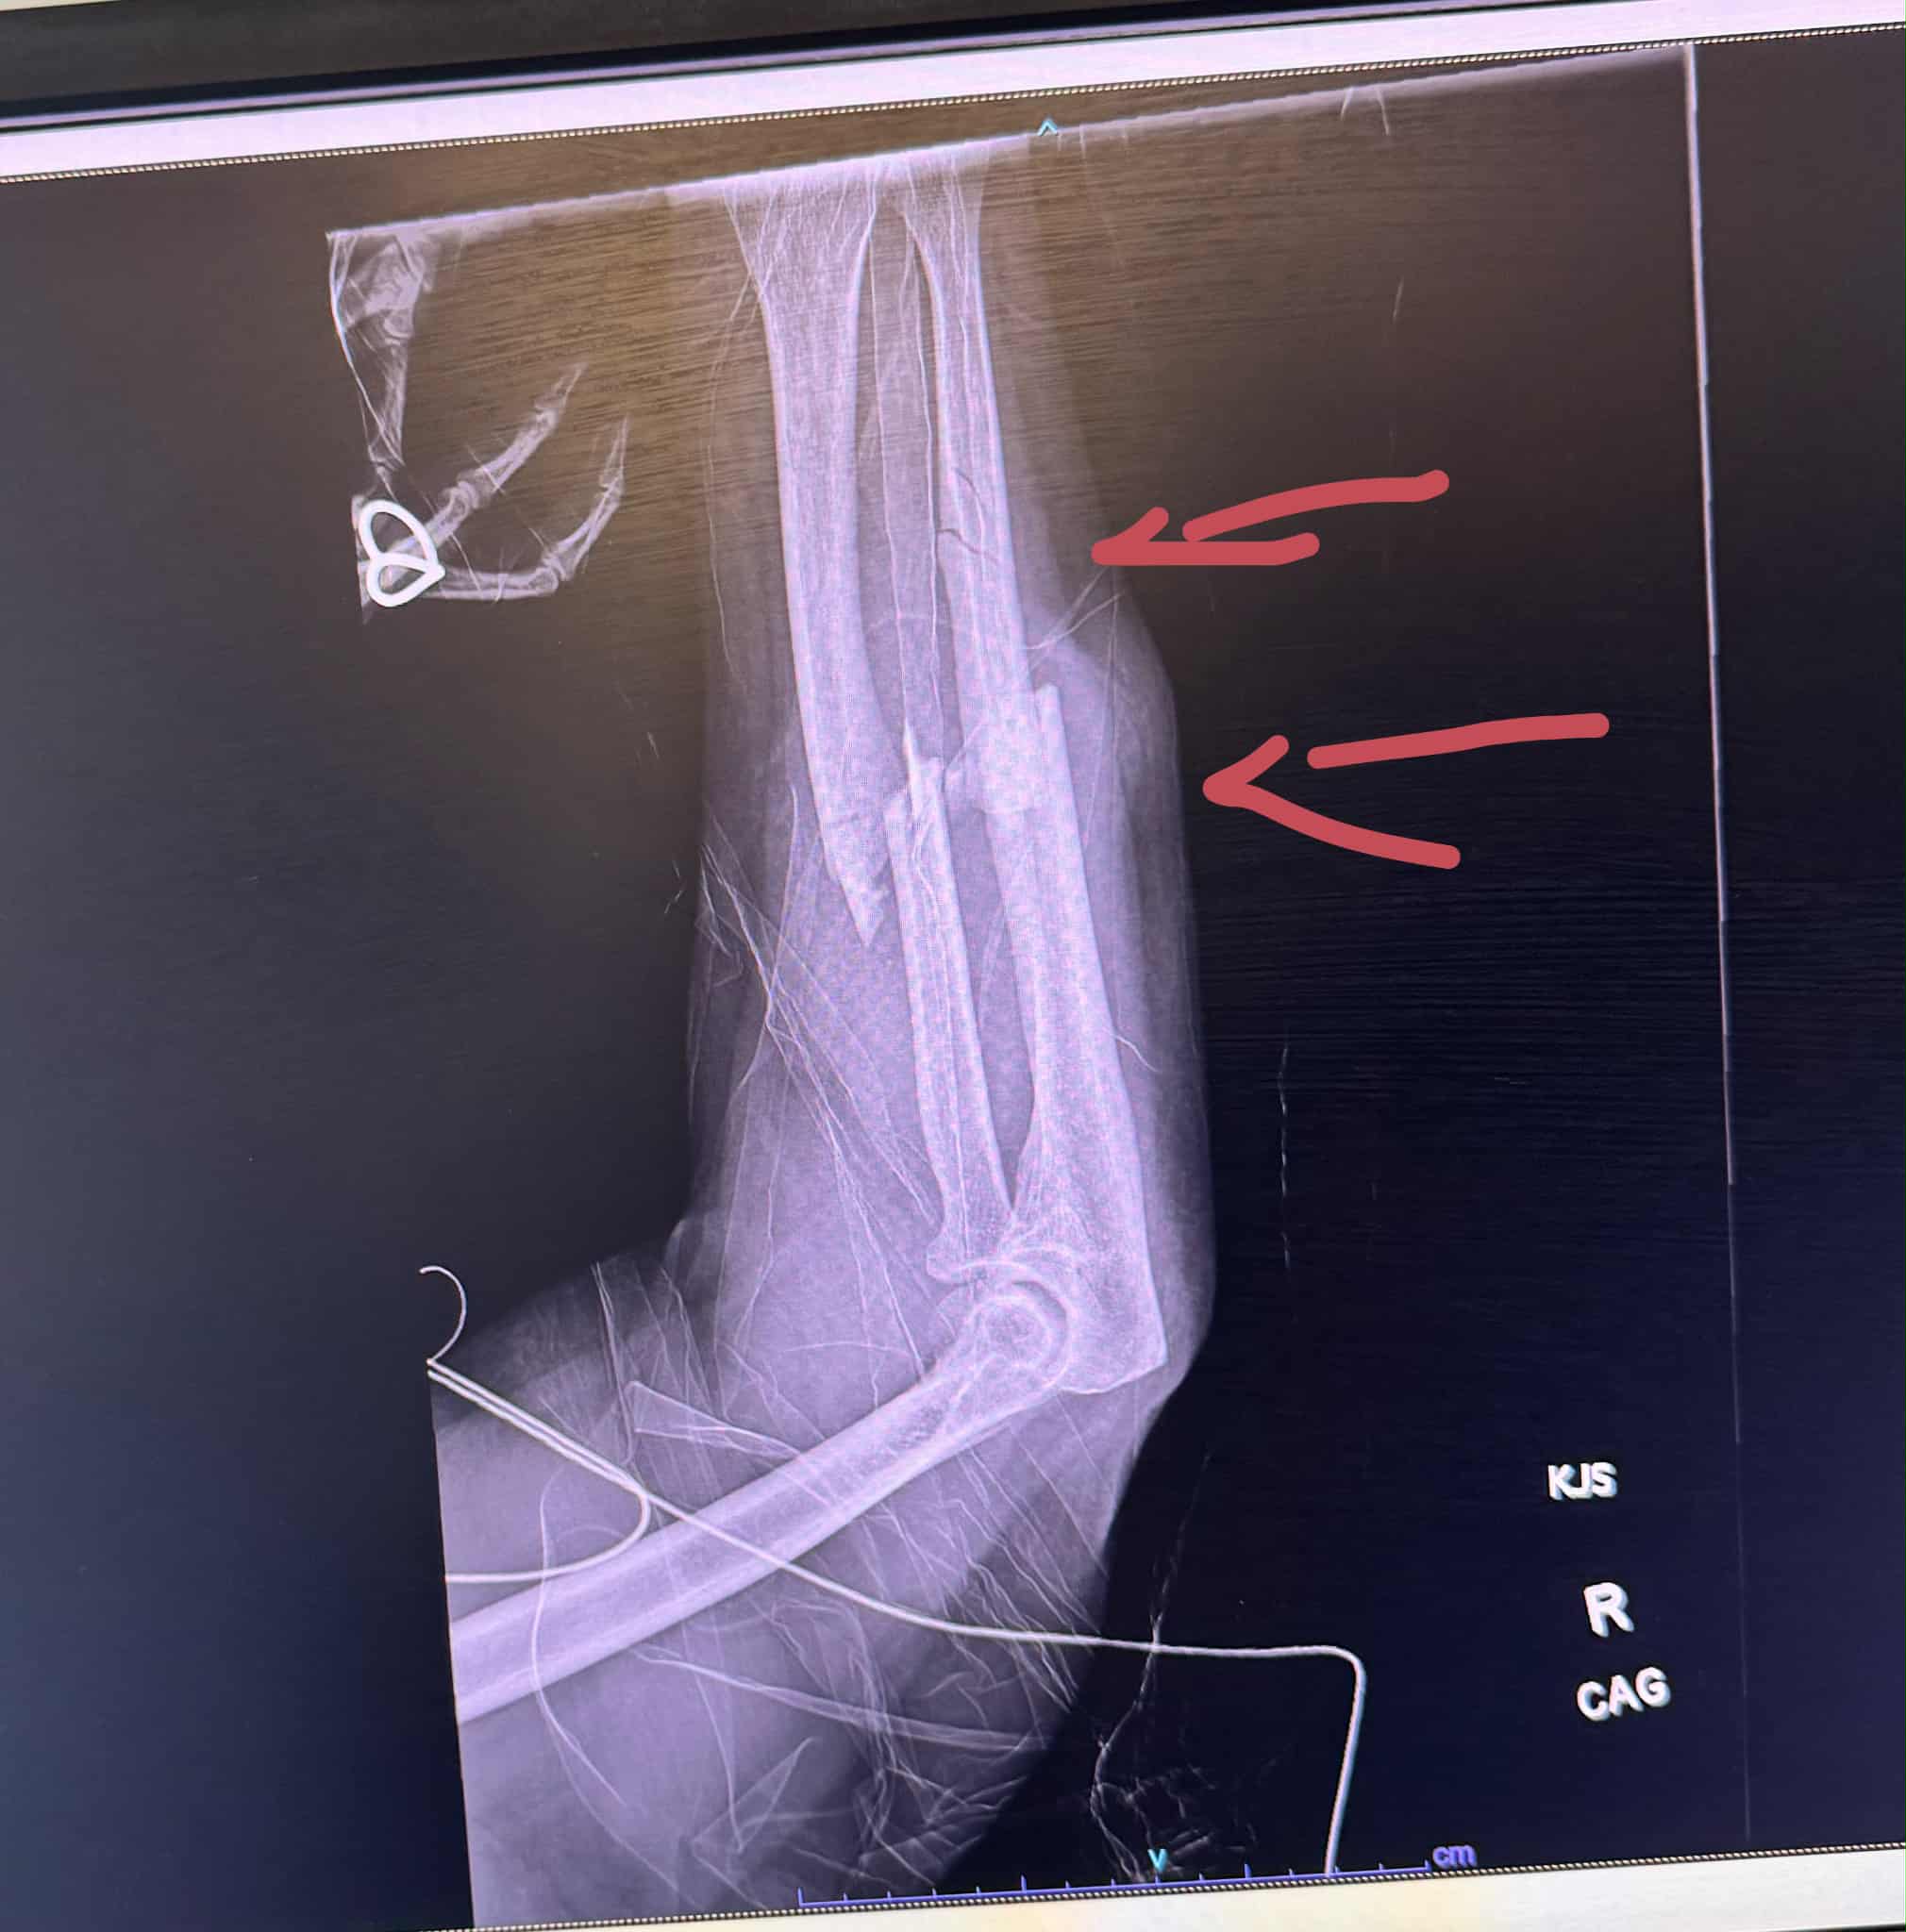

- A shattered arm requiring metal plates

A shattered arm requiring metal plates.